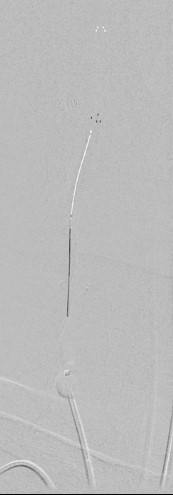

Выполнена реканализация проводником правой ВСА с применением проксимальной защиты. При помощи микрокатетера выполнена тромбоэкстракция из правой ВСА стент- ретривером 6-20(Рис 5.). Удалены тромботические массы. В клиноидном отделе (С 3 сегменте) правой ВСА атеросклеротическая бляшка со стенозом 95%, СМА окклюзирована.(Рис 6,7.) Тромбоэкстракция из СМА справа с полной реканализацией.( mTICI3) (Рис 8,9.) Далее выполнено стентирование правой ВСА стентом 7,0-40мм., с дальнейшей постдилатацией баллоном 6,0-20мм. (Рис 10.) После предилатации баллоном 2,0-10(результат:остататочный стеноз70%) , выполнено стентиование клиноидного отдела правой ВСА баллонорасширяемым стентом 3,0-18мм., постдилатация 3,5-16мм. (Рис 8и9).

рис. 5 рис. 6